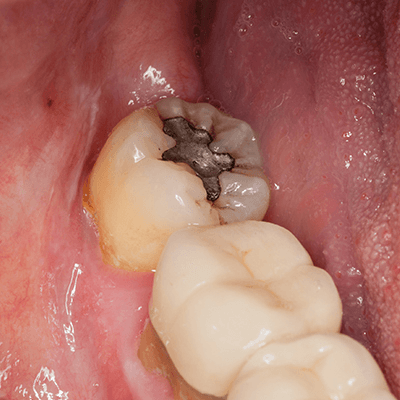

Second: Dental Fillings

Fillings are a restorative treatment used to repair teeth that have already been damaged by decay or trauma. While sealants are placed to prevent cavities from forming, fillings are used to treat existing cavities and restore the tooth’s structure and function.